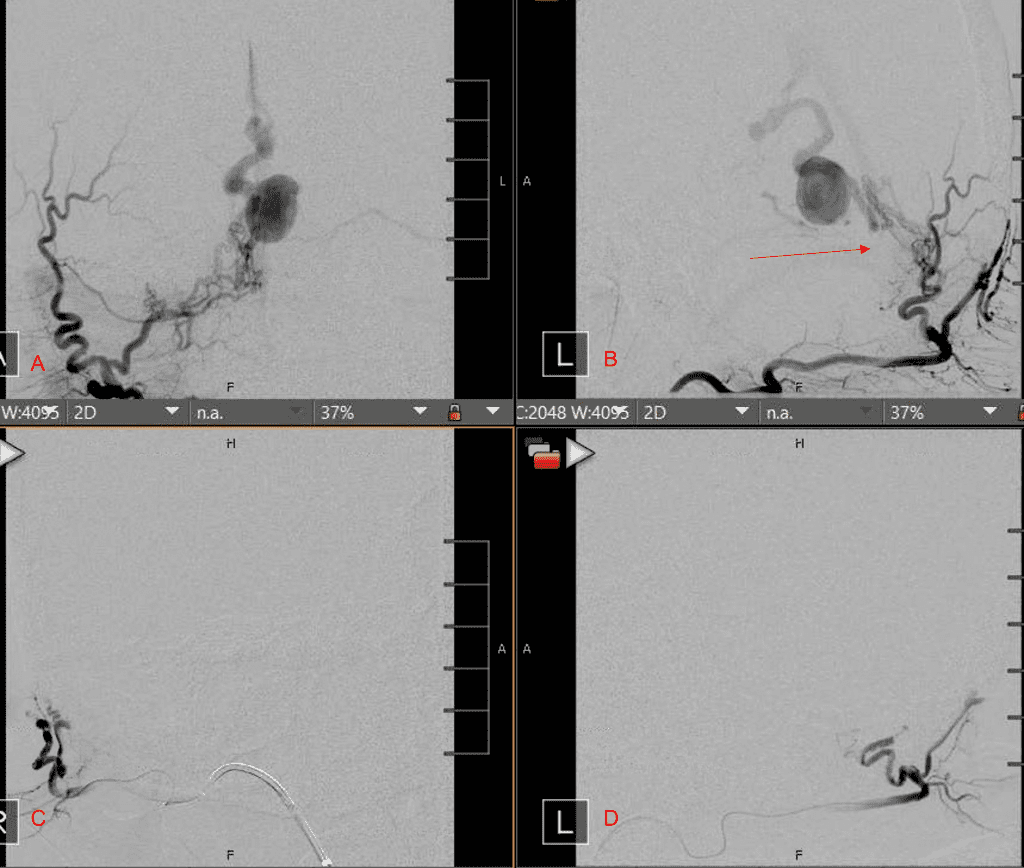

Figure 6. MRI and Catheter Angiograms precisely localize the residual A-V shunts vessels to perform Gamma-Knife Radiosurgery to deliver therapeutic doses to the targets.